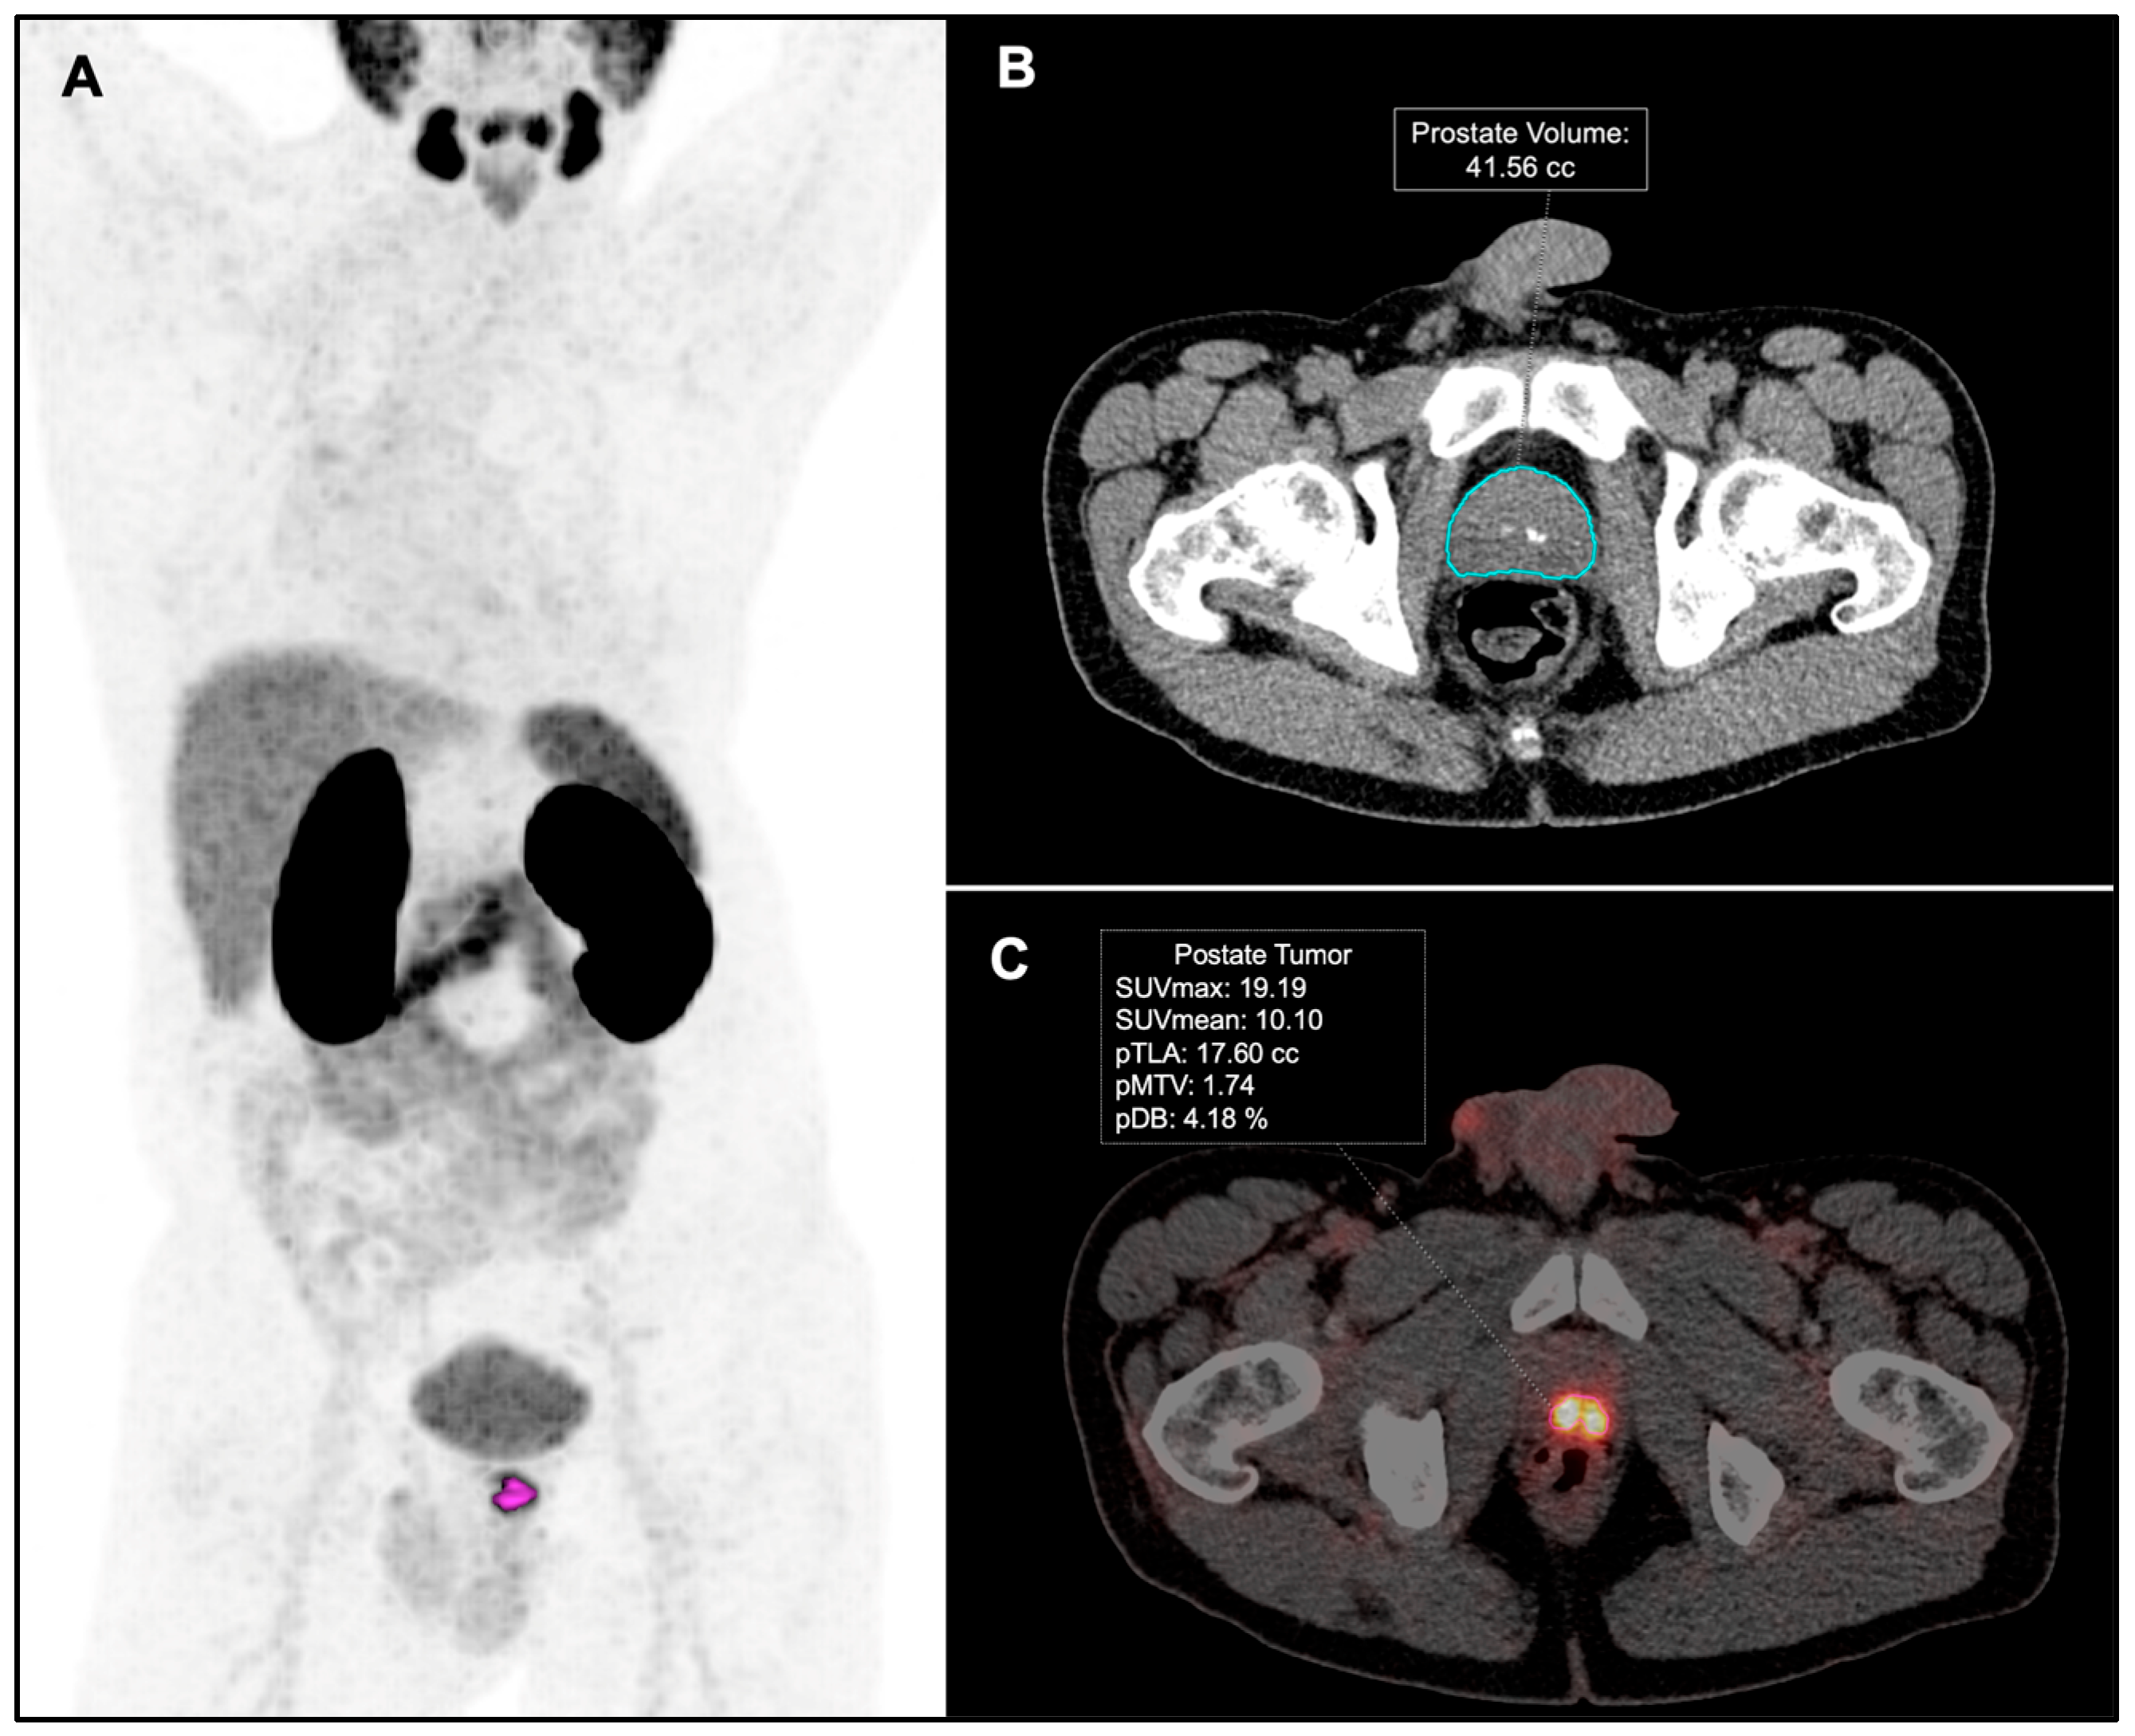

2.3. Image Analysis